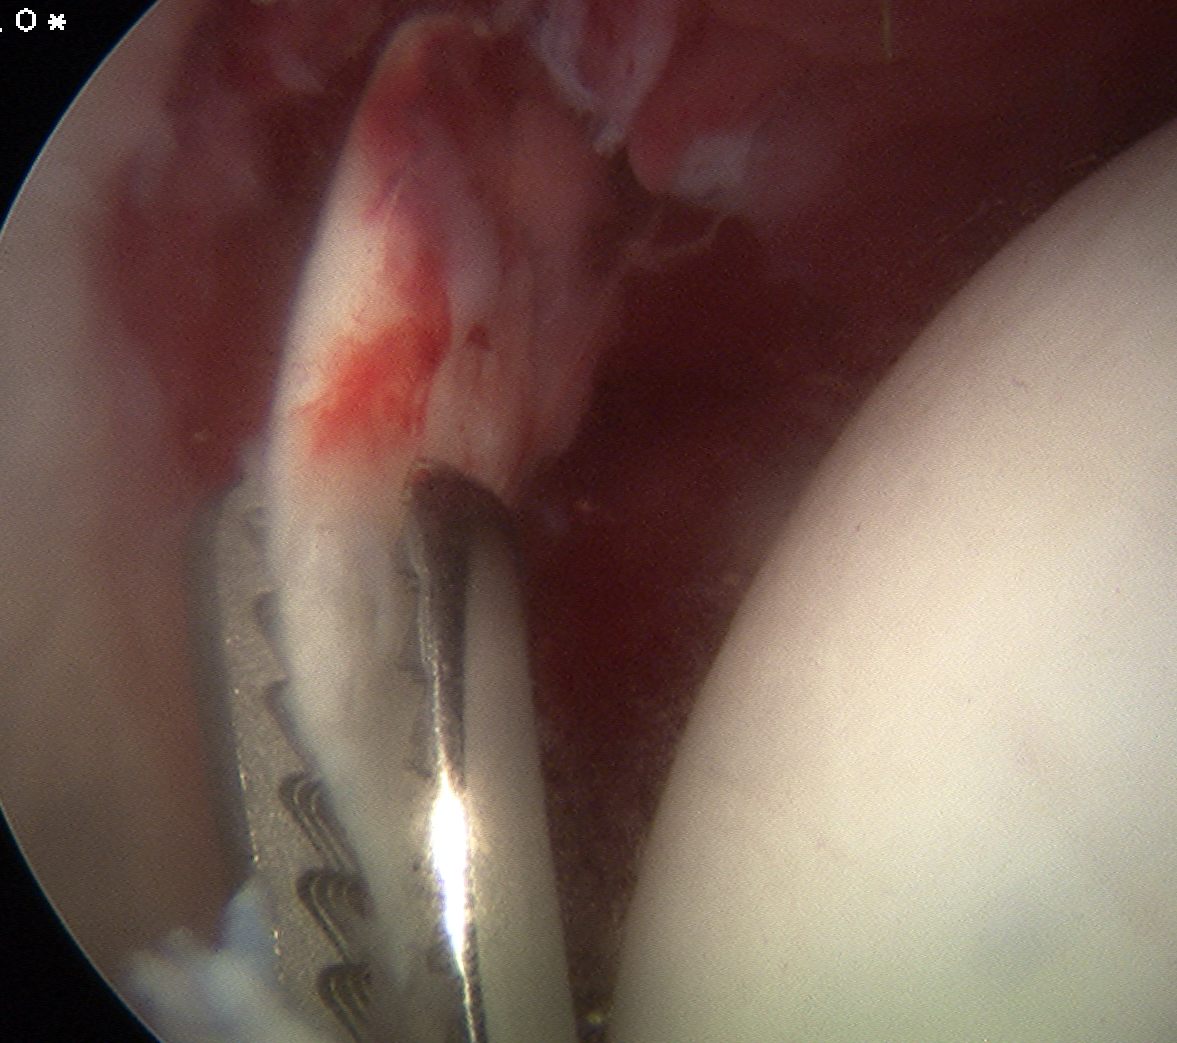

Removal loose body post trauma

- removal of loose bodies

Posterolateral portal